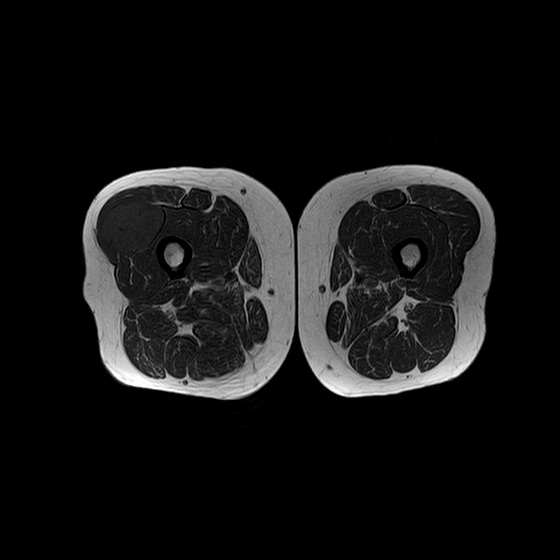

¿QUÉ SECUENCIA EVIDENCIA MEJOR LA LESIÓN?